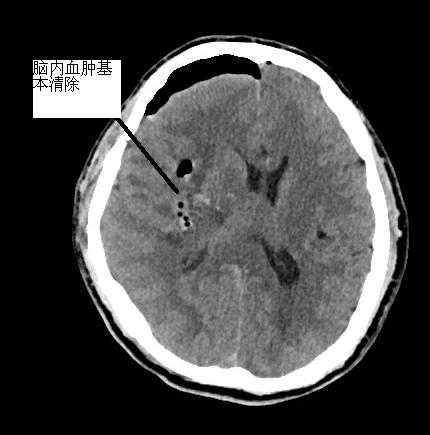

神經(jīng)外科團(tuán)隊(duì)與專家組聯(lián)動,術(shù)前準(zhǔn)備的同時,專家從泉州趕赴我院。到院后第一時間將患者送入手術(shù)室。術(shù)中見手術(shù)視野壓力高,腦組織受壓,予內(nèi)鏡下充分清除血腫、止血,見腦組織壓力減低,腦血管搏動有力,手術(shù)順利。術(shù)后患者無需特殊設(shè)備維持,神志漸清,后經(jīng)康復(fù)治療,患者神志清楚,對答配合,左側(cè)肢體肌力較前恢復(fù)。

▲手術(shù)后原血腫位置,血腫已基本清除